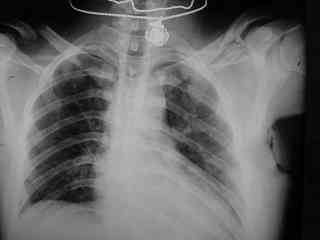

C> Postupil ko mne bolnoi s perelomom obeih kluchits, neznachitelny

C> pneumotorakx sleva.

Накостный остосинтез обех ключиц в одну сессию рекон.пластиной в условиях интубационного наркоза с положительным ПДКВ (+ 5-7 мм вод. ст.) и интраоперационным контролем степени пневмоторакса. Возможно, дренирование плевральной полости слева, по результату рентгенконтроля, по Бюлау.

Справа перелом практически поперечный, можно попробовать интрамедуллярно стержнем. Личного опыта правда не имею, у нас стандартом при оперативном лечении переломов ключицы является тот же остеосинтез пластиной. Но в литературе описана методика даже закрытого остеосинтеза - так, в порядке обсуждения.